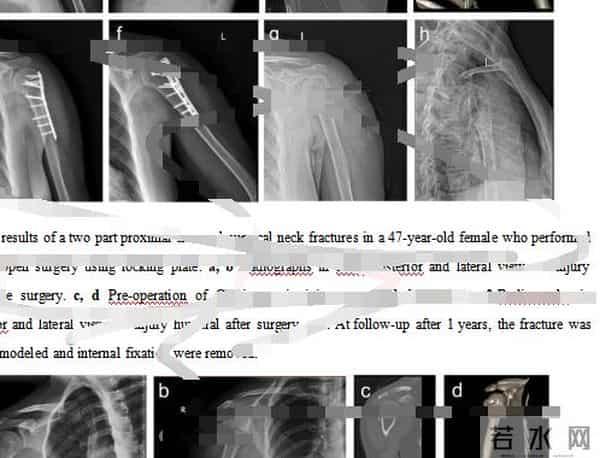

在另一家“论文工厂”,当记者表示着急想发医学方面顶级期刊,对方推荐给记者一篇已基本写好的颈部骨科研究英文论文,并发来部分内容供记者审核评阅,总“标价”3.75万元。

“论文工厂”发给记者的一篇已基本写好的颈部骨科研究英文论文的部分内容